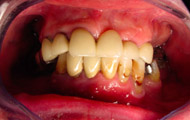

Exemple d’une réhabilitation complète implantaire

Situation clinique initiale